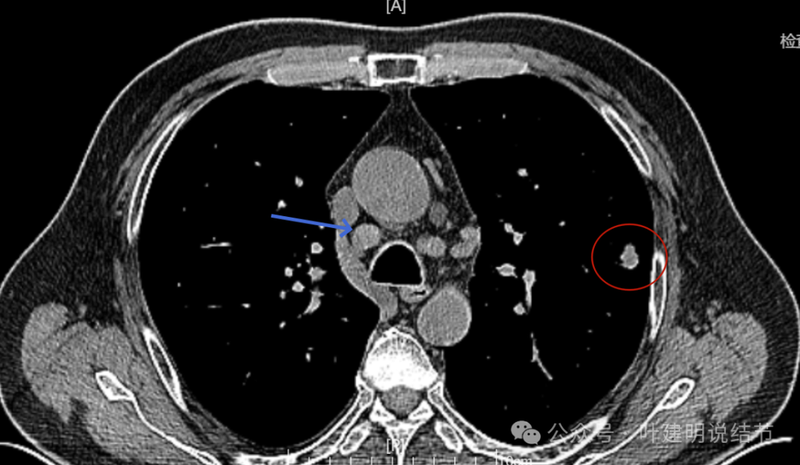

回顾看2023年10月时左上叶此处略有异常,微小实性结节,有血管与之相连。

右上叶另有实性结节,密度较高,边缘略显糊。

纵隔窗见为实性密度,同时见右侧纵隔腔静脉旁明显肿大淋巴结(蓝色箭头)。

回顾2023年右侧纵隔肿大淋巴结也是有的,而且大小与2024年9月的相仿。